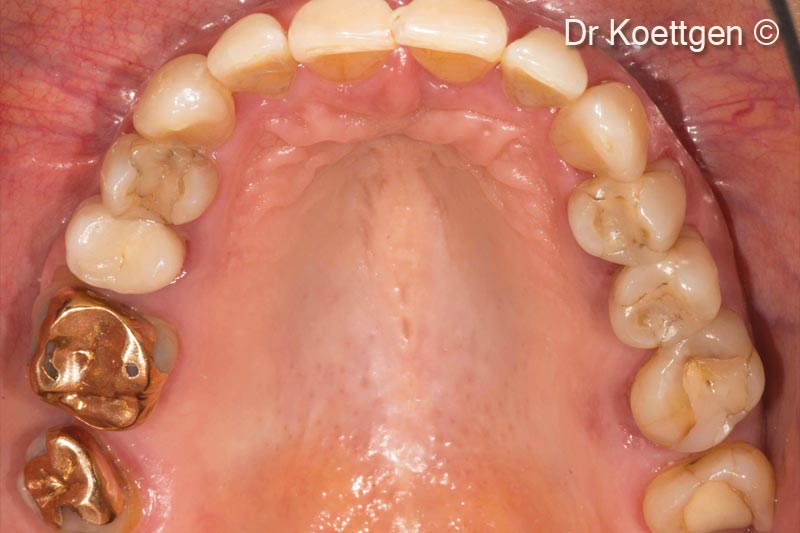

Tình hình ban đầu

Sau khi nhổ răng, bệnh nhân nữ (63 tuổi) cần tăng cường mô cứng và mô mềm.